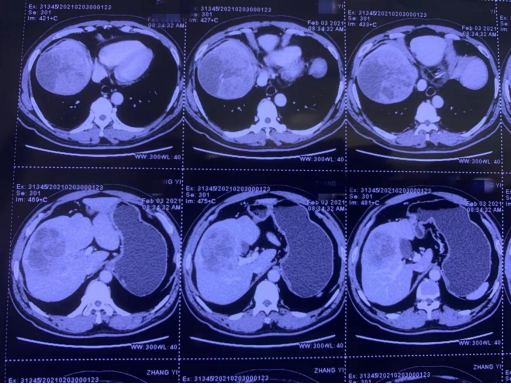

刘先生术前ct片子,肿瘤直径达14厘米

这让刘先生慌了神,经过多方打听咨询后,他选择来到ac米兰官网中文网站二院胆胰外科。经过全面的检查,确诊刘先生右肝有一个直径约14厘米的肿瘤,肿瘤大到已经侵犯左肝内叶、门静脉癌栓。

化疗科为刘先生制定了免疫治疗和靶向治疗联合的帕博利珠单抗与仑伐替尼的组合(“可乐”组合)。在经过三个周期的转化治疗后,经过CT检查发现,肿瘤缩小3厘米,门静脉癌栓也已经退缩到肝内,根治性切除肿瘤有了希望。